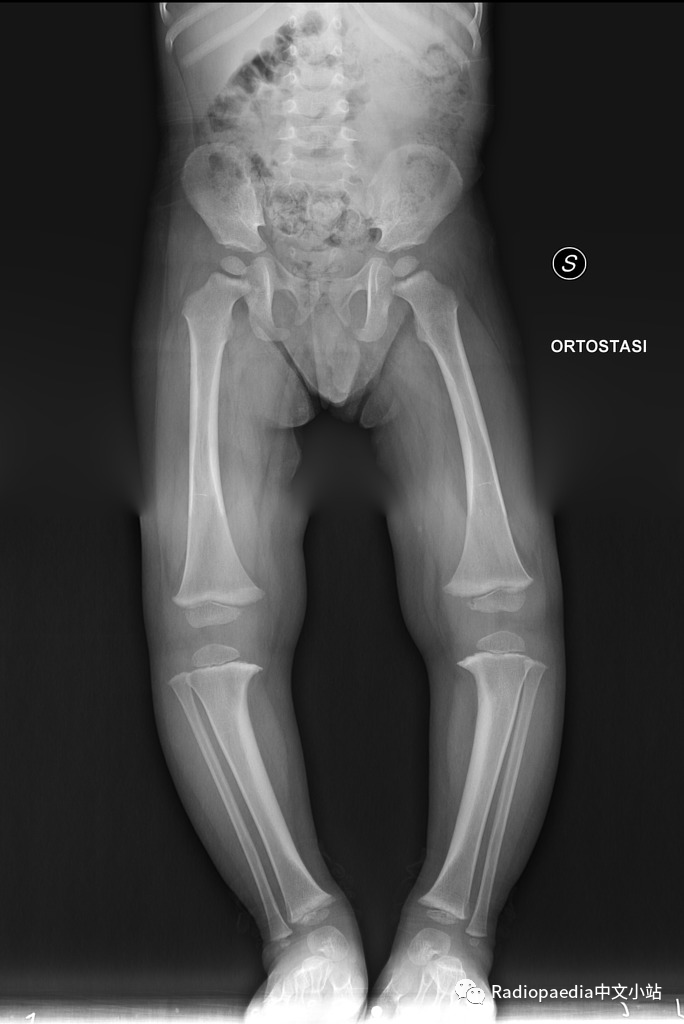

年龄:2岁性别:男病史:O型腿,走路困难

X线

X线见双胫骨内翻,双胫骨近侧干骺端增宽,内侧皮质增厚呈鸟嘴样

胫骨干骺端-骨干角

胫骨干骺端-骨干角:通过胫骨近侧干端的最宽处画条直线(连接内侧和外侧尖状突起处),该线与胫骨长轴的垂直线形成的角度,用于诊断Blount病。胫骨生理性弯曲(2岁以下常见)时,这个角度大约为5°,当大于11°提示 Blount病,大于20°可确诊。但是,一些研究已经开始质疑干骺端-骨干角的有效性,因为该角度的测量可能受到胫骨旋转的影响。

结论:Blount病

婴儿型Blount病,常为双侧受累(60~80%),但双侧多不对称。多有家族史,见于1~3岁婴幼儿,危险因素是过早走路和肥胖。需要与生理性弯曲相鉴别。

当临床出现进展性内翻,同时平片中胫骨近端出现特征性改变(干骺端内侧增宽、规则,骨皮质增厚且呈垂直走形呈鸟嘴样;内侧骨骺高度减小)时可以明确诊断。